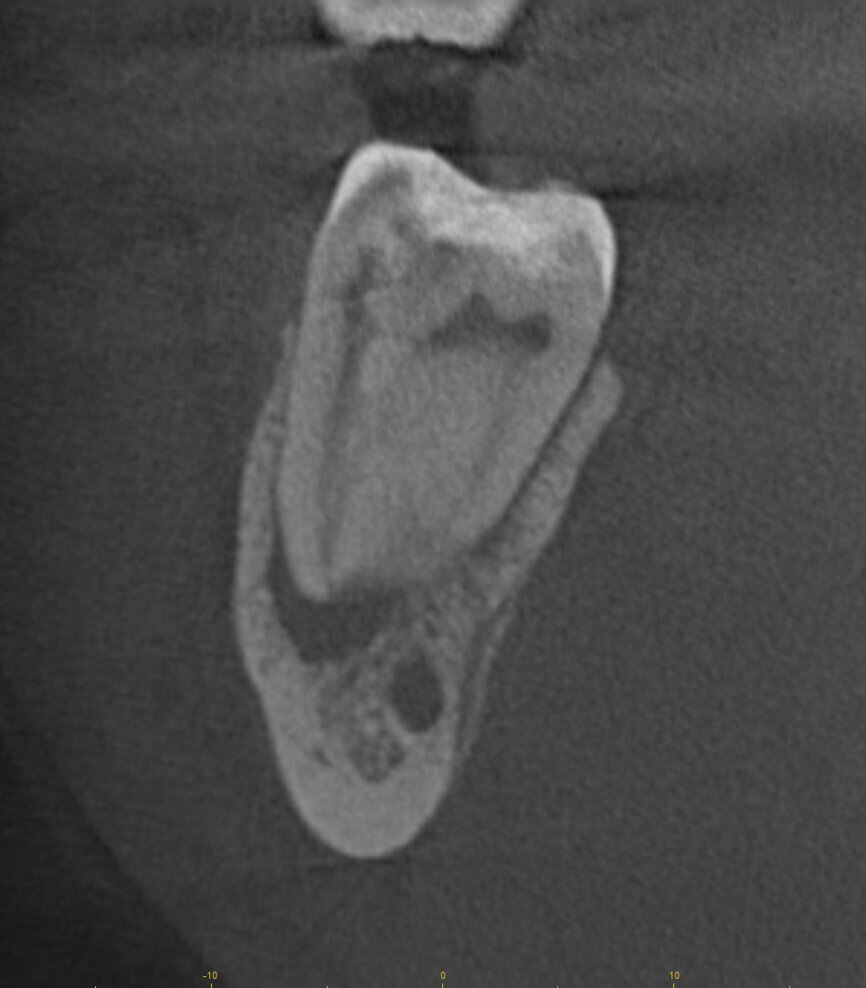

Fig. 17a: Case assisted with CBCT to determine anatomy pre-operatively. Note the multiple cross sections moving apically and the correlation to the 2-D view. Note also the conservative taper in relation to the root width. (Courtesy of Dr. Brett Gilbert)

Fig. 17b: Case assisted with CBCT to determine anatomy pre-operatively. Note the multiple cross sections moving apically and the correlation to the 2-D view. Note also the conservative taper in relation to the root width. (Courtesy of Dr. Brett Gilbert)

Fig. 17c: Case assisted with CBCT to determine anatomy pre-operatively. Note the multiple cross sections moving apically and the correlation to the 2-D view. Note also the conservative taper in relation to the root width. (Courtesy of Dr. Brett Gilbert)

Fig. 17d: Case assisted with CBCT to determine anatomy pre-operatively. Note the multiple cross sections moving apically and the correlation to the 2-D view. Note also the conservative taper in relation to the root width. (Courtesy of Dr. Brett Gilbert)

Fig. 17e: Case assisted with CBCT to determine anatomy pre-operatively. Note the multiple cross sections moving apically and the correlation to the 2-D view. Note also the conservative taper in relation to the root width. (Courtesy of Dr. Brett Gilbert)

Fig. 17f: Case assisted with CBCT to determine anatomy pre-operatively. Note the multiple cross sections moving apically and the correlation to the 2-D view. Note also the conservative taper in relation to the root width. (Courtesy of Dr. Brett Gilbert)

Managing complex anatomy is much simpler if the clinician has a pre-operative road map. The CBCT provides the roadmap and the surgical microscope the lens (literally) through which to visualize the result. Aside from a relaxed patient who is profoundly numb, being able to visualize anatomy by taking a pre-operative (and possibly intra-operative) CBCT and using a surgical microscope during treatment have no substitutes. They are the current “Gold Standard” in that 3-D imaging shows the clinician the true reality of a clinical situation as opposed to the suggestion gained from a 2-D radiograph. Proper interpretation of imaging prior to and/or during endodontic treatment goes a long way in taking the “guesswork” out of identifying canal location and other anatomical complexities as the procedure unfolds. In a 2014 study by El Fayad and Johnson, it was determined that when having a pre-operative CBCT as compared to 2-D radiographs alone, the treatment plan was modified 62 percent of the time. This is a huge game changer to think that the information learned from 3-D imaging changed the plan of treatment over six times out of 10 (Fig. 4).[2]